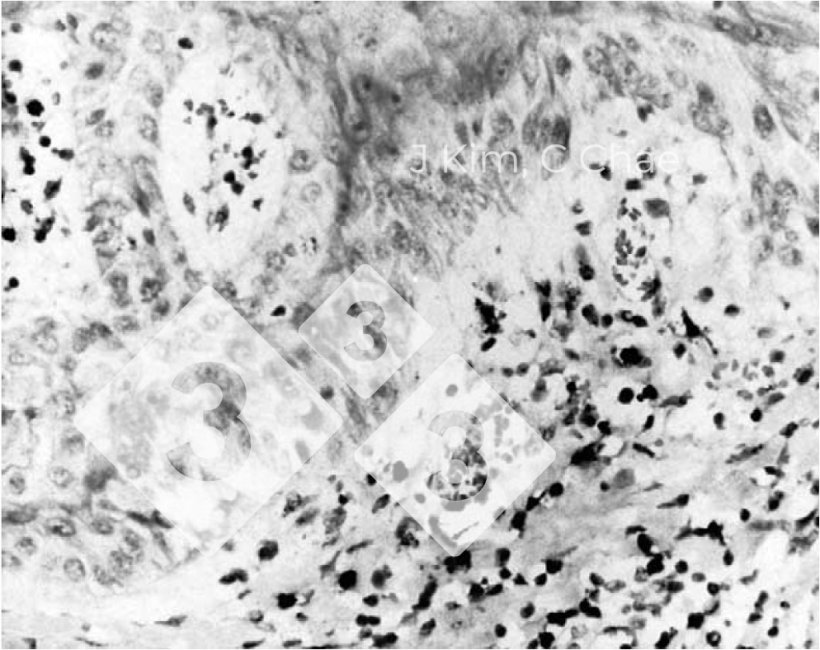

Em 2004, Kim e Chae investigaram exaustivamente 142 secções de pele obtidas de suínos a quem foi diagnosticada epidermite exsudativa. Embora o principal agente causador seja o

Staphylococcus hyicus, a presença do PCV2 foi demonstrada em 8,5% das amostras, a presença do PPV em 11,3% ou a infecção simultânea do PCV2 e do PPV em 42,3% dos tecidos.

Encontrou-se uma marcada positividade conjunta tanto para o PCV2 como para o PPV em todas as áreas inflamatórias na junção dermoepidérmica, na derme superficial e ocasionalmente nos macrófagos dos tecidos linfóides. Isto enfatiza ainda mais a elevada prevalência de infecção simultânea pelo PCV2 e pelo PPV em porcos em crescimento e, neste caso específico, em porcos com epidermite exsudativa.